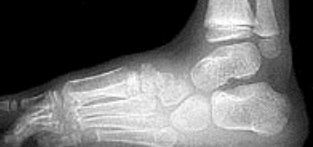

What is this? | Calcaneonavicular coalition (AKA calcaneonavicular bar or anteater's nose) |